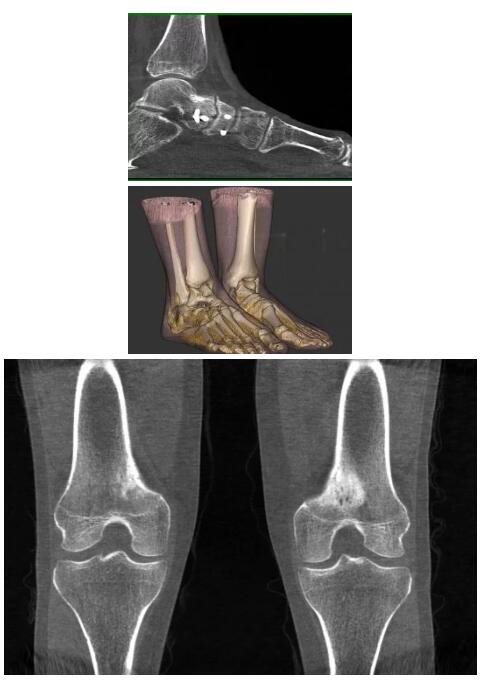

比如上面這款專用于足部和踝部掃查的CT成像系統(tǒng),患者在進(jìn)行CT掃查時(shí)只需要站在上面即可,雙腳站或者單腳站都可以,當(dāng)然,如果患者不是那么方便站著做完CT掃查,也可坐在上面。

這款CT掃查系統(tǒng)自帶屏蔽裝置,它的體積非常小,僅需要極小的空間即可,并不像常規(guī)CT那樣需要一間單獨(dú)的檢查室。此外,這種CT掃查的速度非常快,僅需30秒左右可以完成檢查,輻射劑量相對(duì)常規(guī)的CT要少許多,尤其適合醫(yī)院的骨科使用。

而患者站著做足部或者踝部做CT檢查還有個(gè)好處是,可以檢查患者在負(fù)重的情況下,骨關(guān)節(jié)的真實(shí)情況,而躺著做CT掃查時(shí)未必能看出來(lái)。負(fù)重CT掃查特別是對(duì)于受傷的運(yùn)動(dòng)員或者舞蹈員來(lái)說(shuō)意義更大,能夠更準(zhǔn)確地評(píng)估傷情,幫助他們盡早復(fù)原。

以上介紹的CT均來(lái)自國(guó)外同一家公司,這些CT均配置了可視化軟件,可以進(jìn)行切片、3D重建以及大型CT附帶的所有典型的操作功能。

以下是這些“特立獨(dú)行”的CT所拍出來(lái)的圖像: